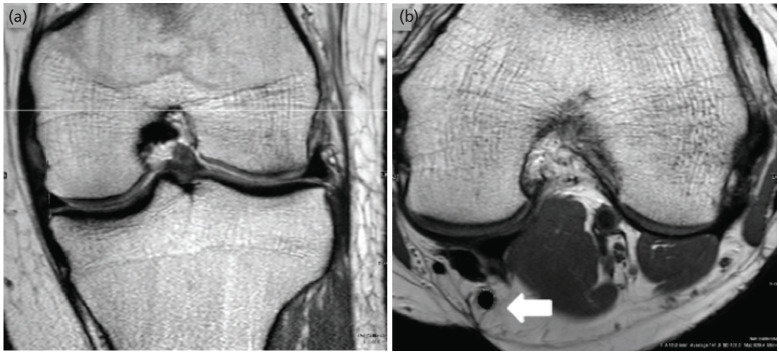

Materials and methods: We retrospectively measured the diameter of the Semitendinosus tendon (ST) on the MRI in all patients who underwent arthroscopic ACL reconstruction using quadrupled Semitendinosus as their graft. We also estimated any correlation between various anthropometric data with pre-operative MRI based Cross Sectional Area (CSA) of the Hamstring tendon and final graft diameter in the South Asian population. The patients were included from Jan 2018 - Dec 2020.

Results: The minimum CSA of ST to predict an eventual graft diameter of 7.5mm was 10.7mm2. The MRI based cross-sectional area measurement showed moderate correlation with the intra-operative graft diameter obtained. (r=0.62, p<0.001). The intra-class correlation coefficient between the radiologist and the surgeon was 0.82, 95% CI (0.57, 0.92) and a p-value <0.001.